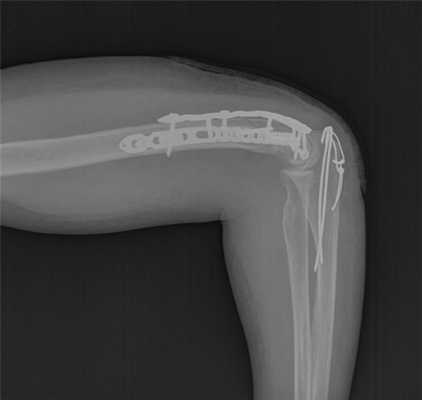

После установки винтов спицы удаляются, так как они уже выполнили свою функцию. Перелом мыщелков плеча надёжно фиксирован винтами и двумя пластинами с угловой стабильностью.

Последним этапом выполняется остеосинтез остеотомированного локтевого отростка спицами и проволочной петлёй по Веберу и послойное ушивание раны.

Такой остеосинтез достаточно надёжен для того, чтобы начать реабилитационные мероприятия уже на следующий день после операции. Ранняя мобилизация локтевого сустава препятствует образованию спаек и позволяет восстановить максимально возможную амплитуду движений в локтевом суставе, что и является целью лечения.